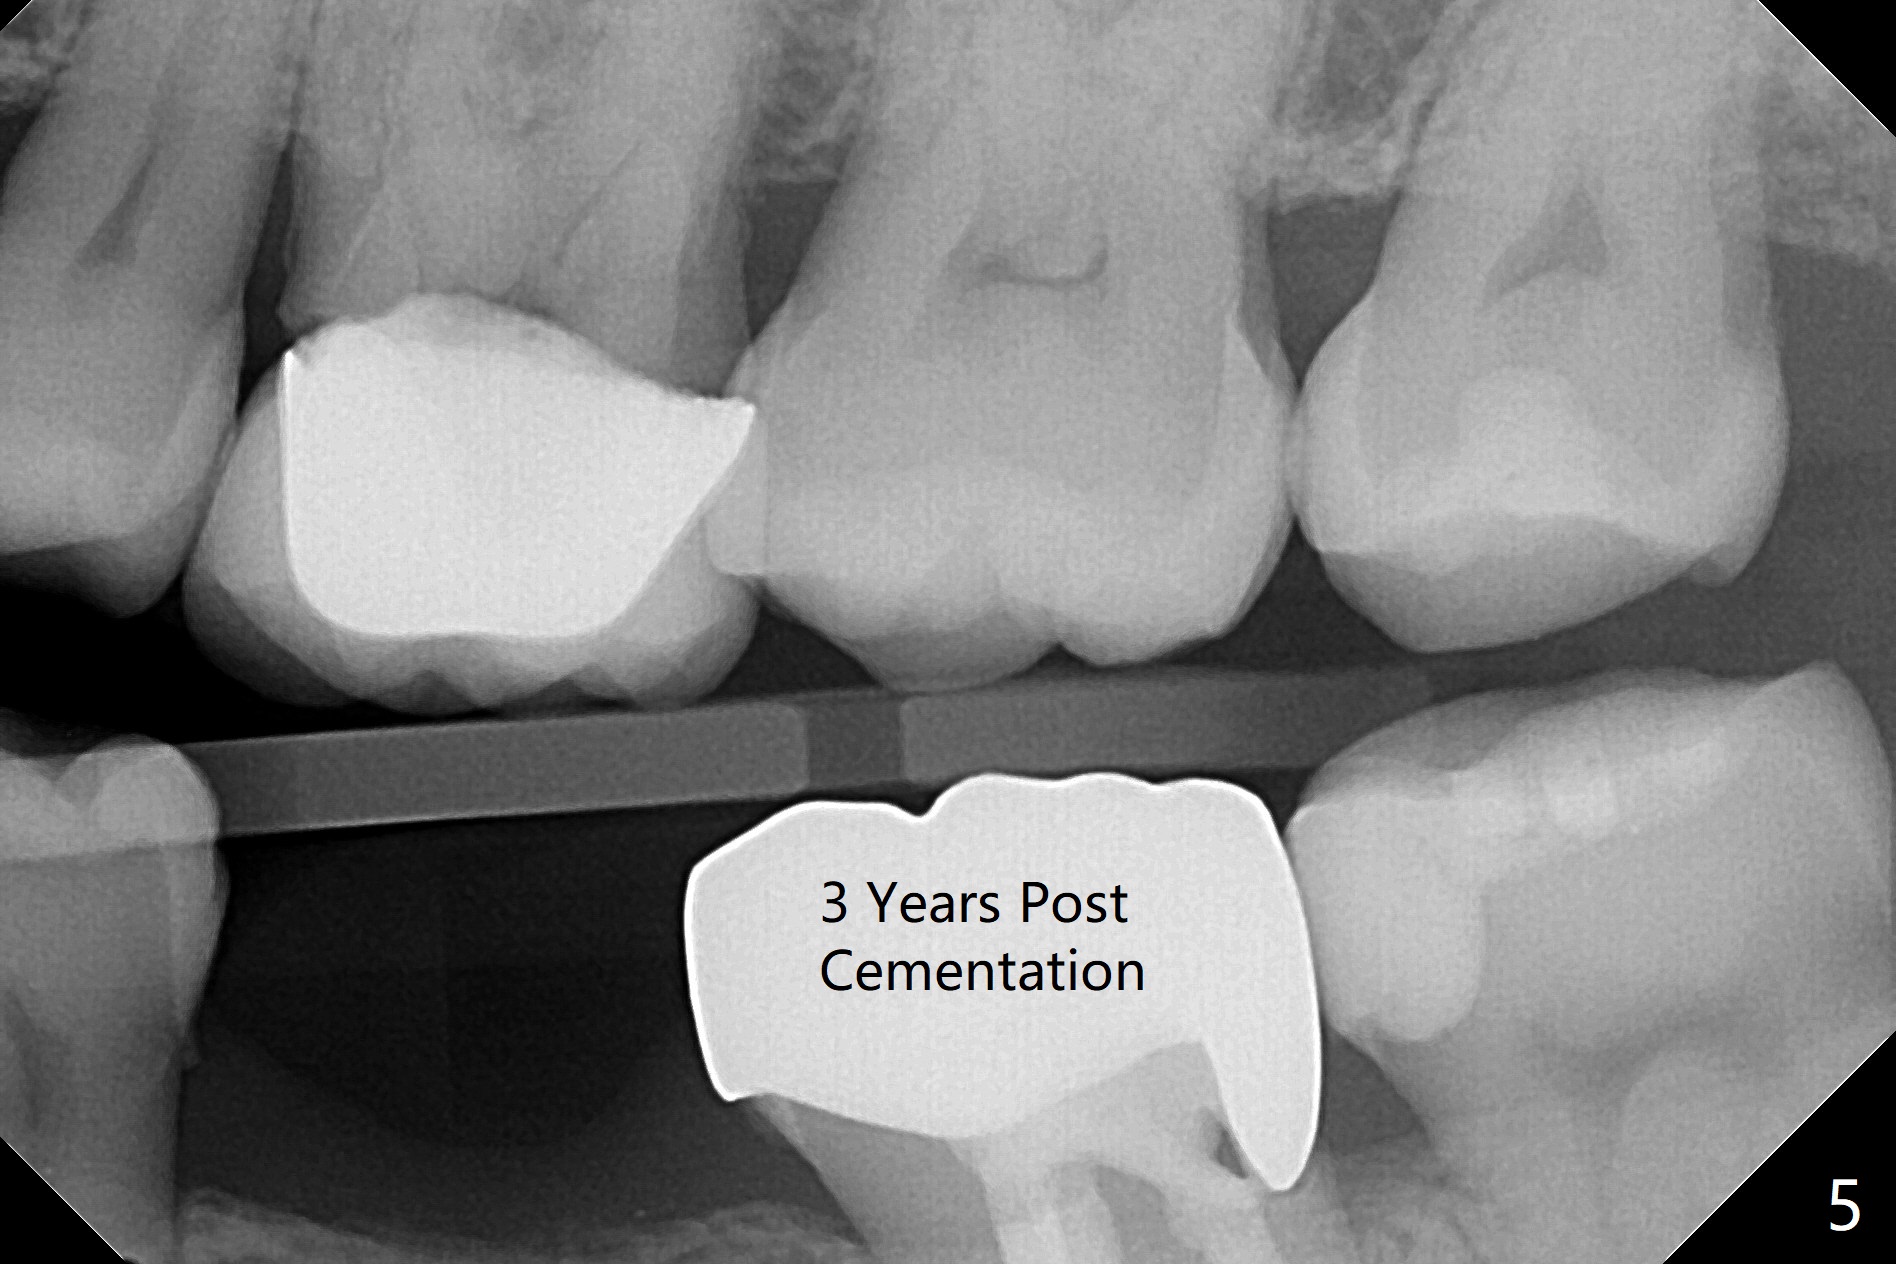

56岁女右上6植牙4年,牙冠松动两次,基台断裂一次,一直不肯做左下6植牙(图一,二,四),对合牙长长(图三:箭头;图五),因为害怕神经(图一:红虚线)损伤,导板已经介绍。IBS No Caries Xin Wei, DDS, PhD, MS 1st edition 11/20/2020, last revision 11/22/2020